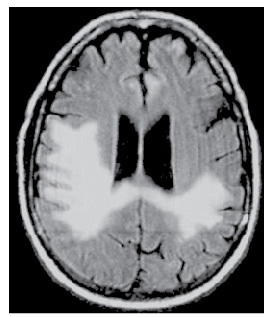

Un patient présente une marche à petit pas, avec anomalie des réflexes posturaux et une ataxie. Une IRM séquence T2: est réalisée: quel diagnostic?

multiples lacunes des noyaux gris centraux car multiples hypersignaux T2

(état lacunaire)